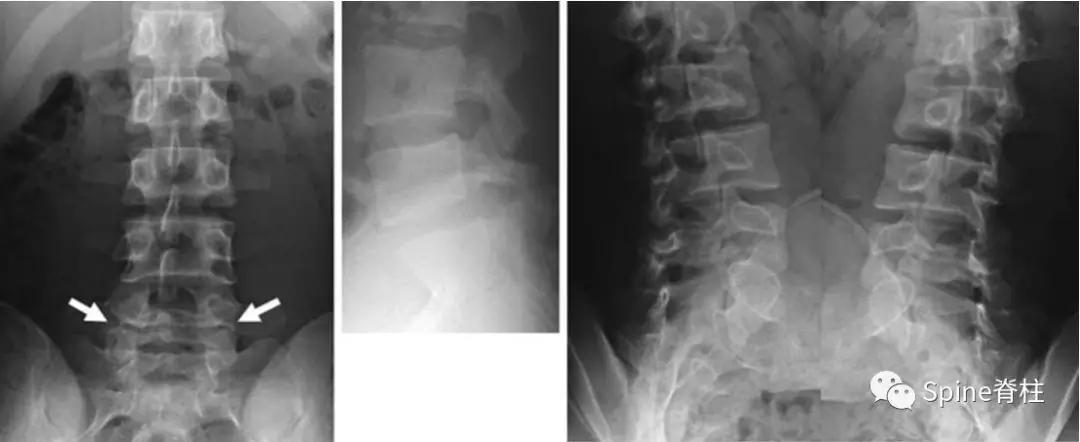

图:17岁男孩,因“腰痛伴右下肢放射痛6个月”就诊

MRI提示腰5-骶1椎间盘突出

青少年与成人LDH都可出现腰腿痛,但 青少年LDH症状通常较轻,神经功能损害(如感觉障碍、肌力下降等)较少见 ,而直腿抬高试验阳性率则可高达90%,而且常呈强阳性,多限于<30°范围。

与成人LDH相比, 青少年LDH患者出现腰椎畸形的比例较高,常见腰部僵硬、脊柱侧凸或旋转,常凸向患侧 ,这种畸形通常是由于疼痛而产生的代偿性脊柱侧凸。

对于以脊柱侧凸为首诊原因的青少年LDH,如果误诊误治会造成严重后果。 此外,腰椎关节突关节不对称的发生率也明显高于成人LDH。

青少年LDH通常仅累及1个节段,最常见于L4-5,少有伴随Modic改变。

青少年LDH以中央型多见,突出物较大,常包含部分骨性结构, 突出的髓核退变不明显,钙化、骨化少见。